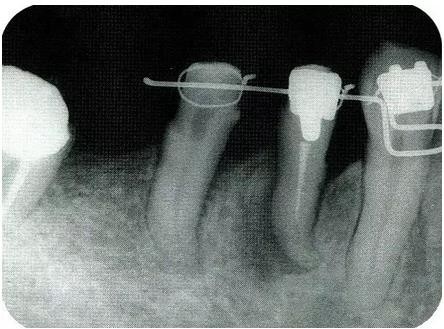

圖18-1(左),2 (右)▲  初診時(shí)口腔內(nèi)照片和X線片,右下4近中有較深的1壁性骨缺損,右下45有根接近。如果在這個(gè)情況下進(jìn)行骨外科處理,需要犧牲較多的右下3遠(yuǎn)中的牙槽骨。也會(huì)造成周?chē)切纬奢^大的臺(tái)階。